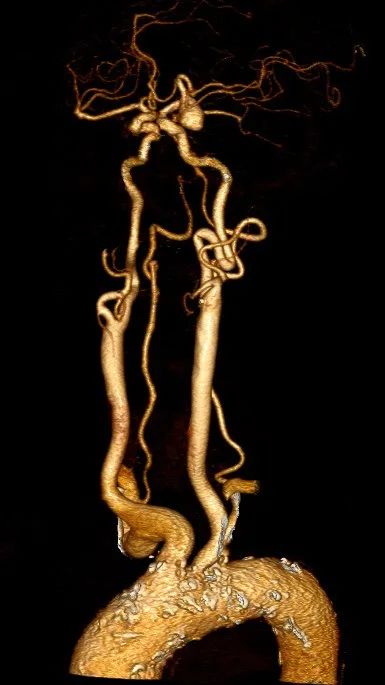

脑动脉CTA示左侧大脑中动脉M1段动脉瘤、左侧大脑后动脉P3段动脉瘤。

左侧颈动脉极度迂曲。

通桥银蛇®DA远端通路导引导管轻松至海绵窦段。